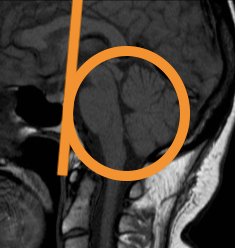

Neuroradiology requires not only familiarity with the normal (MR) image but also understanding of the (patho)physiology. Whenever the physiology of the brain becomes too complicated for me, I go back in embryology to the neural tube, before the neurons and glial cells started to move and intertwine.

In Brain bit by bit vlogs I would like to share and show what I learned and know about different brain diseases, commenting on the radiological macroscopic picture and discussing what happened and happens at the microscopic, invisible cell level. Because this knowledge enables not only recognition of focal, obvious lesions in the brain but also diffuse, subtle disease that has just as much impact on life.

The patient turned out to have an iron metabolism disorder and the first scan was “pre” electroconvulsive therapy.